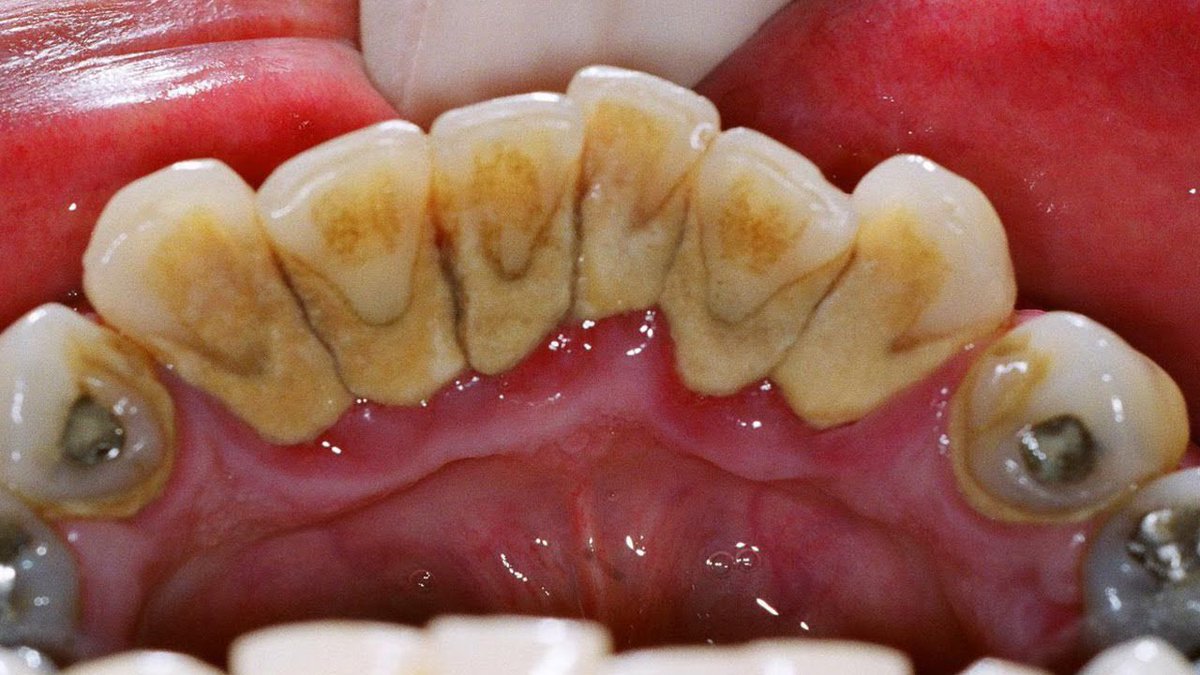

يتكون الجير على الأسنان نتيجة عدم العناية بنظافة الفم فيتراكم البلاك على الأسنان وهو طبقة رقيقة شفافة تتكون من مزيج من بقايا الأطعمة السكرية والنشوية والبكتيريا التي تعيش في الفم، ومع مرور الوقت تتصلب طبقات البلاك نتيجة الترسبات المعدنية التي تتخللها من اللعاب فتتحول إلى جير الاسنان

تشمل أعراض جير الأسنان ظهور ترسبات صلبة وخشنة على الأسنان خاصة بالقرب من اللثة أو بين الأسنان،

قد تظهر هذه الترسبات باللون الأصفر أو البني، حيث أن الجير به مسامات تجعله يتلون بفعل المأكولات والمشروبات التي يتناولها الشخص.

تتضمن أعراض ومشاكل جير الأسنان أيضًا ما يلي:

رائحة فم كريهة.

انتفاخ اللثة وسهولة نزفها.

حساسية الأسنان.

لا تقتصر أضرار جير الأسنان على التأثير على المظهر الجمالي للفم، ولكن تمتد لتشمل مضاعفات تصيب الأسنان واللثة وربما الصحة العامة

يساهم تراكم الجير على الأسنان في تسوسها نتيجة صعوبة القدرة على تفريش الأسنان جيدًا واستعمال الخيط بسهولة.

يؤدي الجير إلى الإصابة بأمراض اللثة، ويعرف مرض اللثة في مراحله المبكرة بالتهاب اللثة وتشمل أعراضه ما يلي

احمرار اللثة وتورمها.🚨

نزف اللثة عند تفريش الأسنان أو استعمال الخيط.